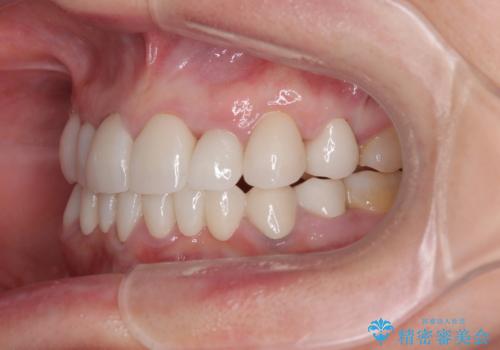

外れるブリッジと気になる八重歯 総合歯科治療で美しい口元に

- 常に外れている下顎のブリッジと、前歯のデコボコと色を気にして来院された患者様です。

前歯のデコボコおよび奥歯の咬み合わせを改善するために、上顎左右の小臼歯を欠損スペースを利用して歯列を整え、矯正治療後に気になる上下前歯などをオールセラミッククラウンで美しく仕上げていくこととしました。

色や歯列が整ったことはもちろん満足いただけましたが、上顎の舌側転位していた前歯が綺麗に整ったことで違和感が減ったことを非常に喜んでいらっしゃいました。